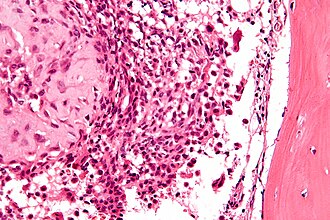

Chondroblastoma. H&E stain. | |

| LM | abundant (chondroid) extracellular material, chondroblasts (variable nuclear morphology (ovoid, folded or grooved), moderate-abundant eosinophilic cytoplasm), +/-calcifications surrounding the cell nests ("chickenwire" appearance) - classic feature, +/-giant cells |

- Abundant extracellular material - pink on H&E stain - looks vaguely like cartilage.

- Sometimes described as 'immature cartilage' (very narrow DDX for this type of cartilage)

- Chondroblasts:

- Nuclear morphology variable: ovoid, folded or grooved.

- Moderate-abundant eosinophilic cytoplasm.

- +/-Calcification surrounds the cell nests ("chickenwire" appearance) - classic feature.

- Cell nests have a thin pale blue rimming.

- +/-Giant cells.

- May lead to confusion with giant cell tumour of bone.

- Not infrequently associated with an aneurysmal bone cyst (33%).[3]